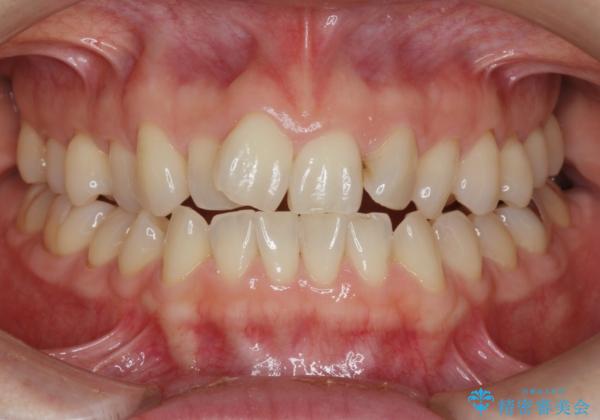

前歯の目立つガタつきをマウスピース矯正で治療

- 大きく傾いてしまった前歯のガタつきの改善を求めて来院されました。

前歯のガタつきをしっかりと取り、機能的・審美的に理想的な歯並びをマウスピース矯正で達成します。

強度のガタつきはマウスピース単体では並び切ることが難しいこともありますが、しっかりと装着していただいたことで良好な治療結果を得ることができました。